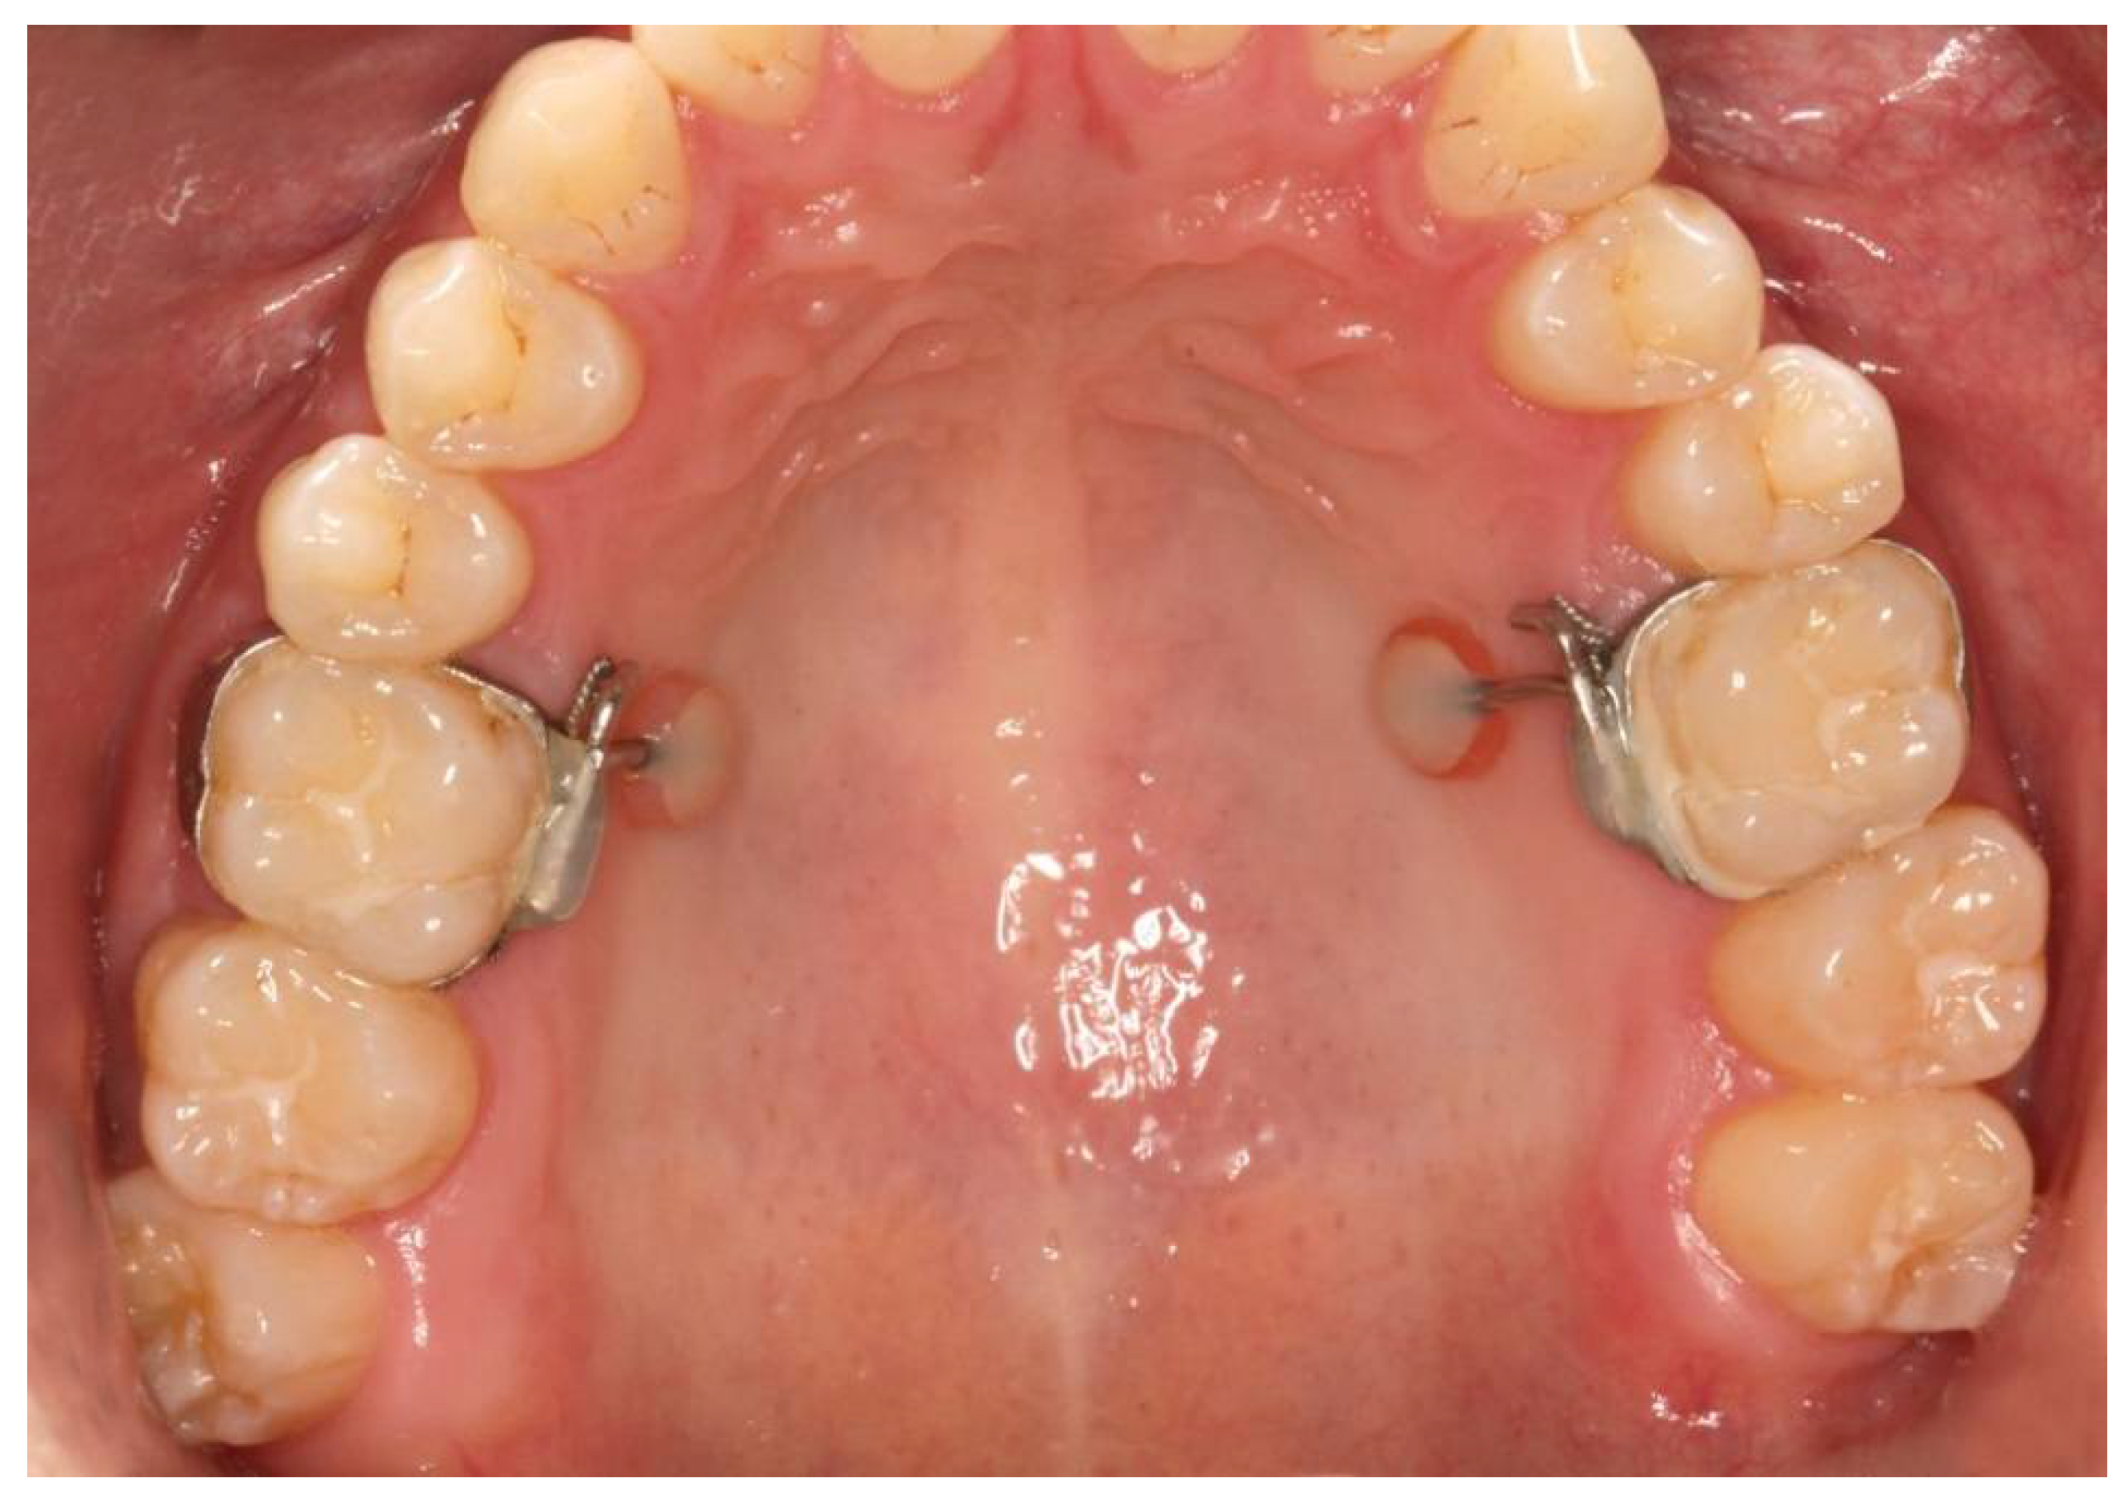

2. Materials and Methods